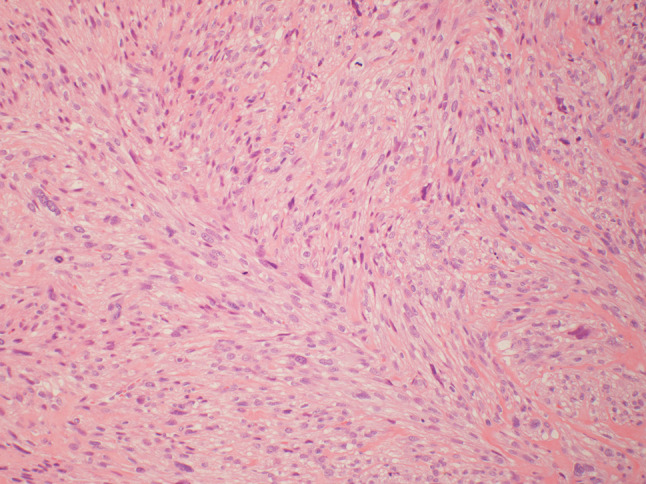

Fig. 2.

At medium power (×100), the spindle cells are arranged in fascicles and contain abundant fibrillary eosinophilic cytoplasm. The nuclei tend to be oval with perinuclear vacuoles. Mitotic figures are common as are scattered cells with marked nuclear atypia